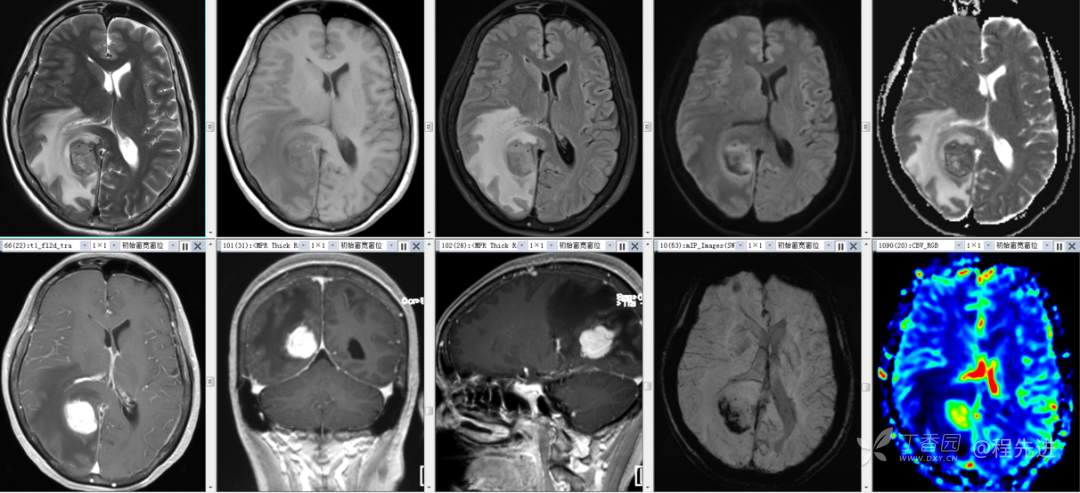

辅助检查:外院头颅 CT 示:右侧顶枕叶占位。

颅脑 MRI 平扫+增强: